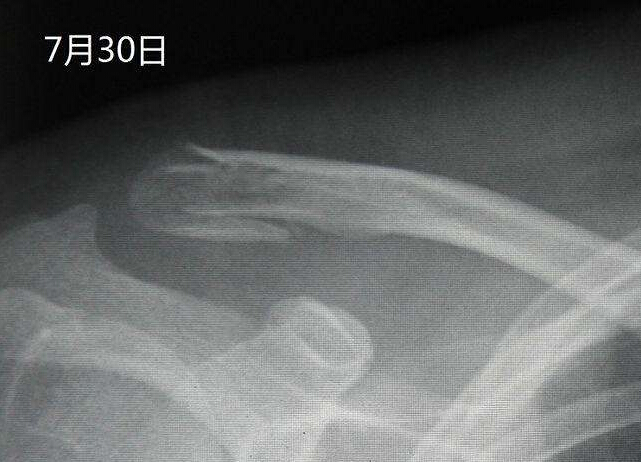

【摘要】通過拍攝X線片,可以了解骨折的部位,骨折線的走向,骨折的移位情況,骨折的類型等,為醫師製定治療方案,監測治療結果提供依據。X線照片一般需要拍攝正位和側位,同時應包括鄰近關節,這樣才能全麵地反映出骨折的全貌。盡管如此,有些骨折還需要加攝特定位置才能顯示骨折線,有些骨折需經1~2周後骨折處骨質吸收才能顯示骨折線。

通過拍攝X線片,可以了解骨折的部位,骨折線的走向,骨折的移位情況,骨折的類型等,為醫師製定治療方案,監測治療結果提供依據。X線照片一般需要拍攝正位和側位,同時應包括鄰近關節,這樣才能全麵地反映出骨折的全貌。盡管如此,有些骨折還需要加攝特定位置才能顯示骨折線,有些骨折需經1~2周後骨折處骨質吸收才能顯示骨折線。